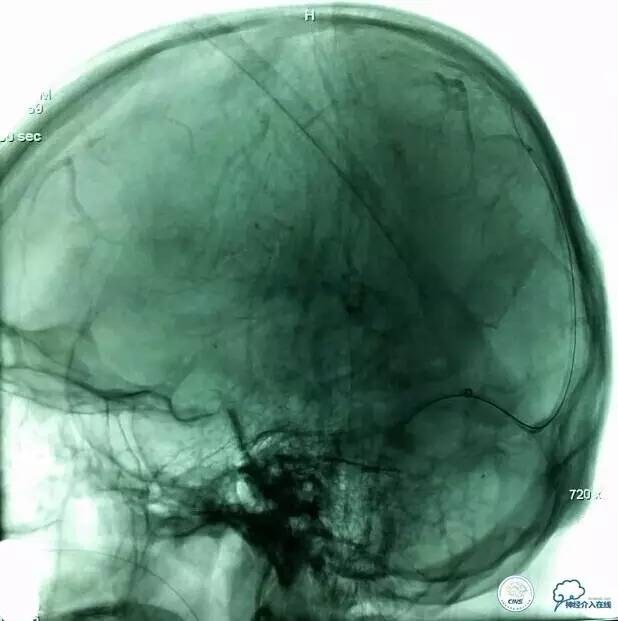

▼术前造影和MRV一致:

▼8F-Guiding 导管+6F-Navien 导管到位,微导丝选入上矢状位窦内。

▼Solitare6mm-30mm支架放于近端窦汇处,血栓中,5分钟后取栓。